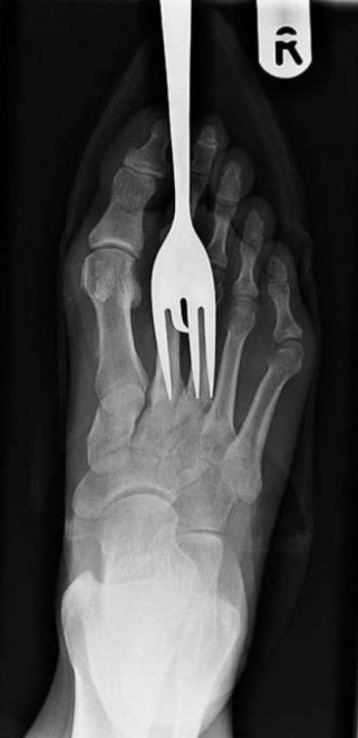

Doktorların görüp yok artık bu nasıl mümkün olur dedikleri röntgen filmleri..

Doktorluğun zor bir meslek olduğu malum. Üstelik bu mesleğin icra ederken bazı zamanlar öyle vakalar ortaya çıkmış ki, doktorlar bile anlamlandırmakta zorluk çekmişler.